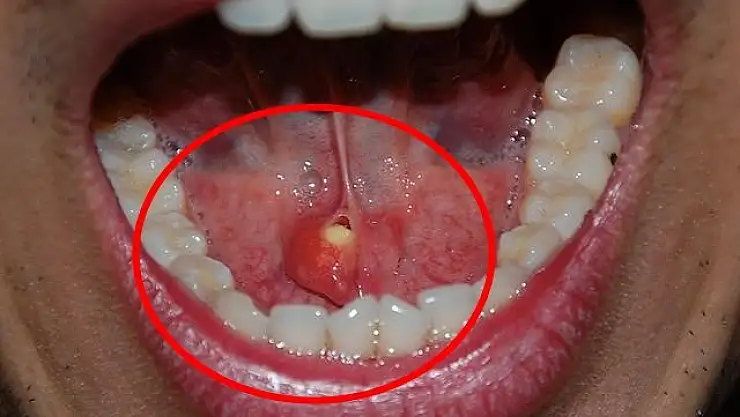

Taşların ağızdan dışarı atılmasındaki yöntemler hakkında da bilgilendirmede bulunan Doç. Dr. Nesrettin Fatih Turgut, “Bu hastalıkta tipik belirti, taşın var olduğu tarafta yer alan bezde yemek yeme sonrası gelişen şişlik ve ağrıdır. Tükürük salgısının dışarı atılamayıp birikimi, enfeksiyona yatkınlık oluşturur. Bakteriyel tükürük bezi iltihabı dediğimiz hastalık gelişebilir ki bu durumda şikayetler şiddetli hale gelebilir. Etkilenen tükürük bezinin aşırı şişmesi, aşırı hassasiyeti, ağrı ve ateş gelişebilir. Tedavi edilmediği takdirde, hastane yatışı gerektiren ve şiddeti daha fazla olan bir tabloya, derin boyun enfeksiyonuna, ilerleme görebiliriz. Şikâyetleri daha hafif olan ve taş boyutları küçük ve tükürük bezi kanalının ucuna yakın yerde yerleşim gösteren hastalarda geleneksel tedaviler önerilir. Ağrı kesiciler fayda sağlar. Bol sıvı tüketimi, ısı uygulaması rahatlama sağlayabilir. Bol sıvı tüketimini tüm hastalarımızda önermekteyiz. Aynı zamanda limon gibi ekşi ürünlerin emilmesi tükürük sıvısını artırır ve çok küçük taşların dışarı atılmasını sağlayabilir. Taş boyutunun büyük olması, taşında daha çok beze yakın yerde yerleşmiş olması durumlarında ise cerrahi uygulamaları gündeme gelmektedir. Taş yerleşimi, büyüklüğü etkilenen tükürük bezinin durumu cerrahinin şeklini belirler. Eğer taş tükürük bezi kanalında yer alıyorsa, sialendoskopi olarak adlandırılan kamera sistemi ile yer tespiti ve çıkarma işlemi herhangi bir kesi olmaksızın tercih edilir. Ancak taşın tükürük bezi içerisinde yer alması, boyutunun çok büyük olması durumlarında ise dışardan veya ağız içinden yaklaşım ile cerrahi seçenekleri gündeme gelmektedir” diye konuştu.

Tedavi yöntemlerinden de bahseden Turgut, “Sialendoskopi, genellikle tükürük kanallarında taş olan hastaların tedavisinde kullanılmaktadır. Ayrıca sjögren hastalığı, radyoaktif iyot tedavisi almış hastalar ve tekrarlayan tükürük bezi iltihaplarına sahip çocuk hastalarda da bu yöntem uygulanabilir. Büyük taşlar havalı kırma tekniği kullanılarak küçültülerek çıkarılır, bu nedenle işlem süresi uzun olabilir. Sialendoskopi sırasında herhangi bir kesi veya dikiş uygulanmaz, bu nedenle işlem sonrasında ağrı veya şikâyet gözlemlenmez. Geçici olarak aynı taraftaki tükürük bezinde şişlik olabilir, ancak genellikle bu şişlik 1-2 saat içinde azalır. Hastalar, genellikle aynı gün içinde taburcu edilirler. Taş boyutunun büyük olması, taşın bez içinde yerleşim göstermesi, sık enfeksiyona bağlı taşın kanala yapışık olması gibi nedenlerden dolayı sialendoskopi ile taşın çıkarılması mümkün olmayabilir. Bu durumlarda açık cerrahi seçeneği gündeme gelir. Eğer taş, kanal içinde yerleşim gösteriyorsa ağız içerisinden kanal üzerinde yapılacak ufak bir kesi ile taşa ulaşılır ve taş çıkarılır. Birkaç dikiş atılarak işlem tamamlanır. Hastalarımız ancak taş tükürük bezi içinde olursa veya tükürük bezi sürekli (kronik) enfeksiyona bağlı olarak işlevini yitirmişse (atrofiye uğramış) tükürük bezi genel anestezi altında çene altından kesi yapılarak tamamen çıkarılır. Ameliyat sonrası 2-3 gün hastane yatışı gerekebilir” şeklinde konuştu.